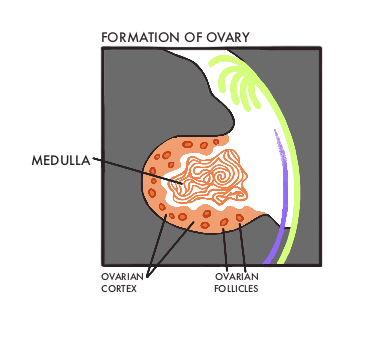

Development of the Genital System